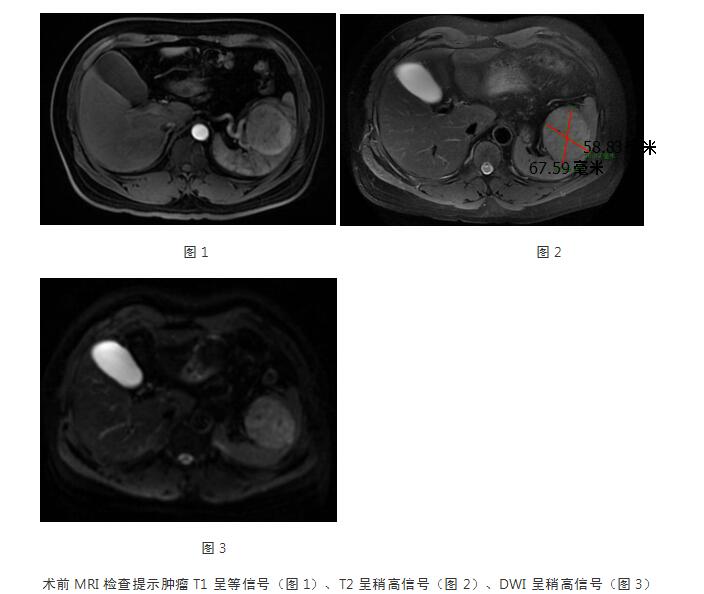

曹明溶主任对梁女士的影像学资料进行详细的阅读后表示,该肿瘤不仅能够通过微创技术切除,还能够保留一部分正常的脾脏,最大限度地减少术后免疫功能的减退。梁女士欣然接受曹主任的治疗方案。